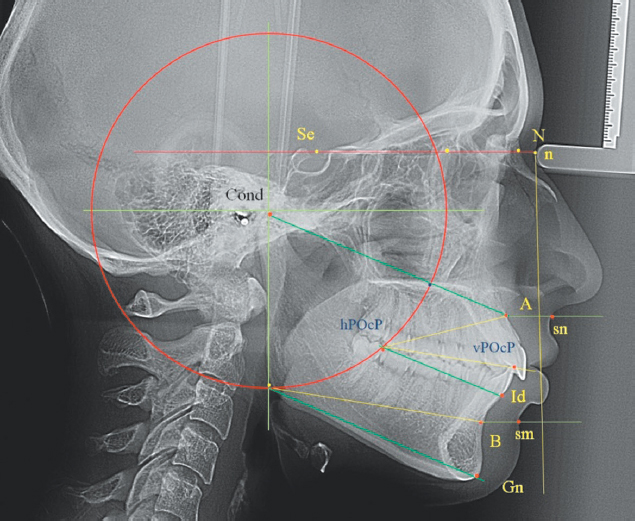

Построение геометрических фигур на боковых телерентгенограммах осуществлялось в компьютерной программе Power Point. На изображении рентгенограммы ставили точечные ориентиры. Линию основания черепа (Se-N) проводили от середины входа в турецкое седло до назальной точки, расположенной в месте соединения лобной кости с носовыми. Указанную линию делили на две неравные части, большая часть которой соответствовала золотому сечению, полученному в результате деления длины основания черепа на число Фибоначчи (1,618). Величина золотого сечения использовалась для определения соразмерности с другими горизонталями лица.

При определении радиуса окклюзионно-суставной окружности измеряли расстояние от верхней точки суставной головки (Cond) до дистальной точки окклюзии второго нижнего моляра с антагонистом.

Определяли положение костных точек апикальных базисов челюстей по проекции апексов резцов на альвеолярную кость. На альвеолярном отростке верхней челюсти указанная точка обозначалась как субспинальная точка Downs (А), а на альвеолярной части нижней челюсти — как супраментальная точка Downs (В). На подбородке использовали точку Gn, находящуюся на передней нижней поверхности симфиза.

От нижней точки диаметра суставного круга в переднем направлении строили линии, соединяющие гнатическую точку подбородка и супраментальную точку Downs.

Окклюзионная линия соединяла молярную и резцовую точки окклюзии. Верхняя окклюзионно-апикальная линия соединяла субспинальную точка Downs (А) с молярной точкой окклюзии (рис. 1).

Рис. 1. Построение окклюзионно-суставной окружности и диагностических линий на боковой телерентгенограмме.

Fig. 1. Construction of the occlusal–condylar circle and diagnostic lines on a lateral cephalometric radiograph.

В качестве вспомогательного ориентира использовалась вертикаль Дрейфуса, располагающаяся перпендикулярно к линии основания черепа и спускающаяся вниз от назальной точки.